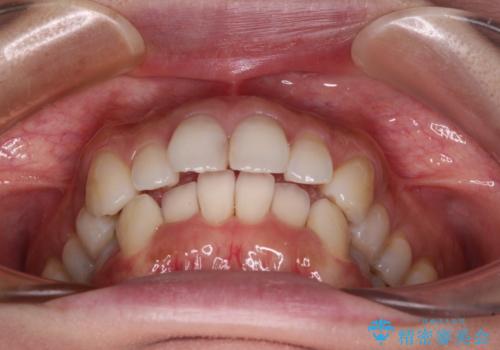

- デコボコと飛び出している前歯を気にして来院された患者様です。

歯列としてはインビザラインでもワイヤー矯正でも対応できるものでしたが、奥歯の咬み合わせを見た時に上顎がやや前方にあり、インビザライン単独では時間のかかってしまう可能性があるため、補助装置を治療当初に使用することで、インビザラインによる治療をスムーズに行えるように計画しました。

インビザラインは得意・不得意の差がはっきりとしているため、補助装置やワイヤー装置などをうまく活用することで、治療期間を短縮するとともに、より理想的な仕上がりを達成することができます。